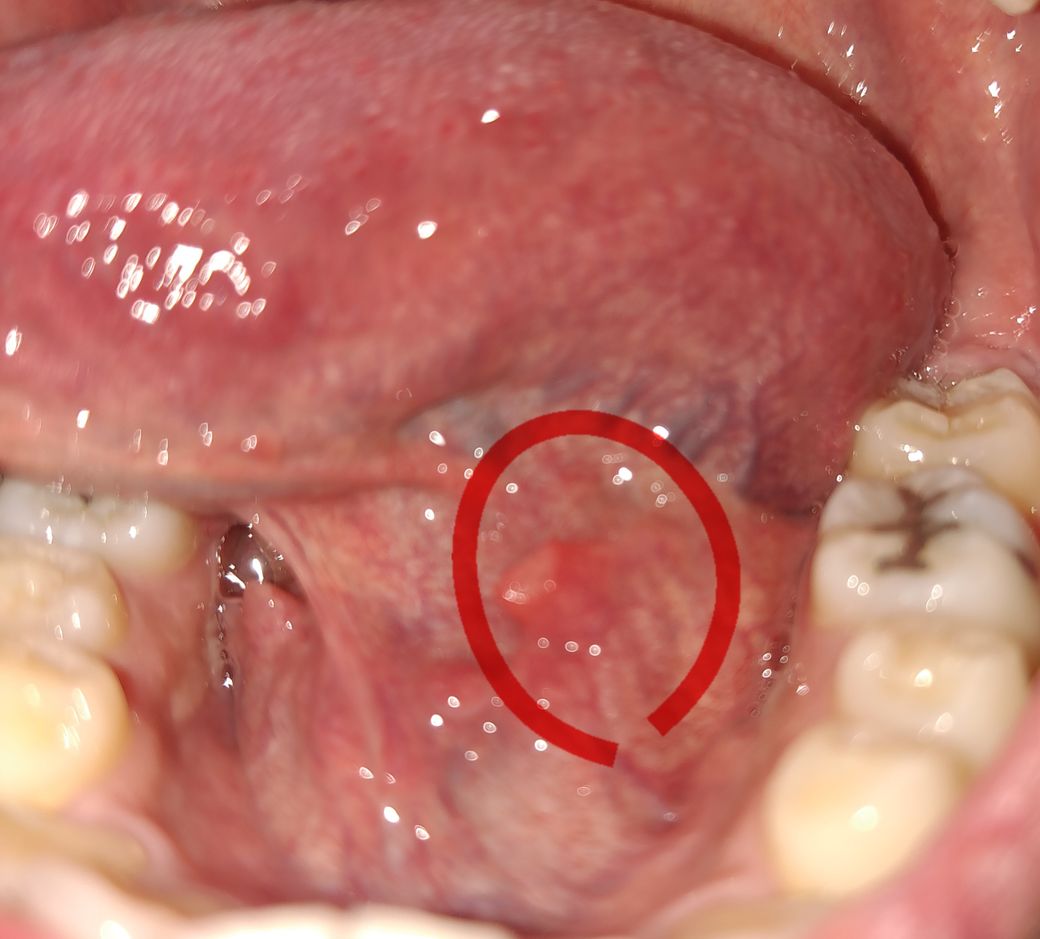

오늘 갑자기 뭔가 혀에 만져져서 봤더니 저런게 생겼어요.. 조금 길쭉한 사각형 모양으로 살이 튀어나왔어요

아프지는 않는데 불편해서 뭔지 너무 궁금합니다.

사진으로 봐선 단순 섬유성 과증식일 수도 있으나 혀 밑 혈관(설하정동맥)과 관련된 질환일 수도 있을 것 같습니다. 구강내과가 진료과로 있는 치과 가서 한번 체크해보시기 바랍니다.

혀 아래에는 저렇게 주름이 잡혀 있는데요. 간혹 해당부위에 염증이 생기기도 합니다. 사진상으로 보기에는 염증이 있는 것으로 보이고 보통 시간이 지나면 괜찮아지니 너무 걱정하지 않으셔도 되겠습니다. 혹시 해당 병소의 크기가 커진다거나 통증이 심해질 경우에는 치과에 내원해보시는 것이 좋겠습니다.